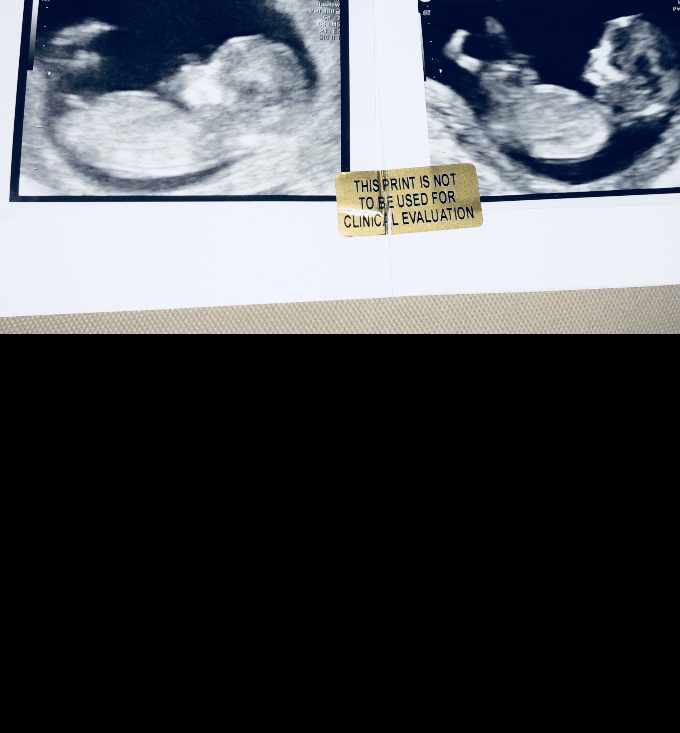

Hi ladies, I’ve attached the pic... does this work? Would love to hear your guesses... xx

This is one of those nubs that I can easily see going either way. Ever so slight boy lean from me but wouldn't be surprised at all if it was a girl. Do you have any more pics?

Feeling boy a bit more strongly based on the top left pic you just posted!